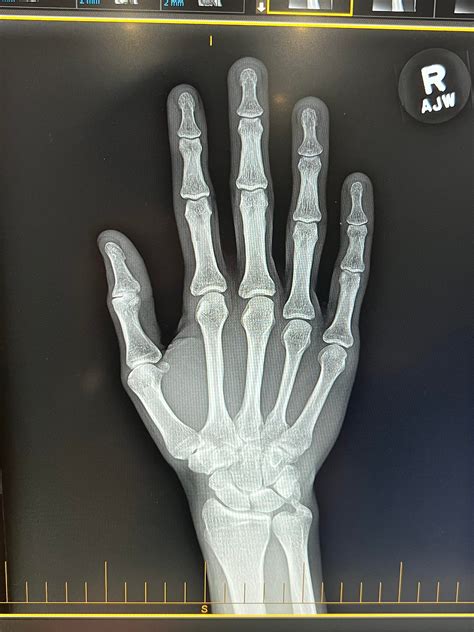

• Imaging Tests: X-rays, MRI, or CT scans may be ordered to visualize the joints and identify any abnormalities.